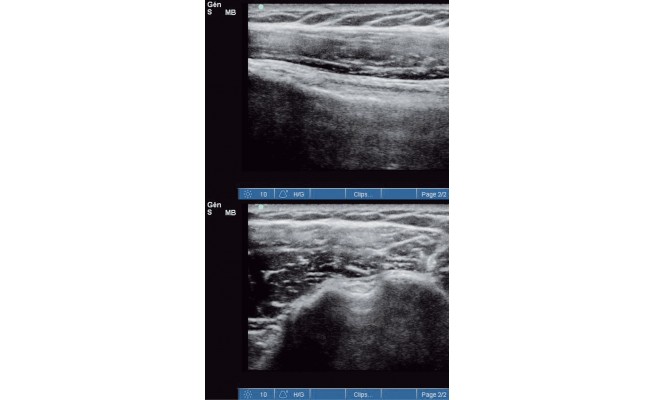

Fig. 1 : Tendon du long biceps dans sa gouttière en coupes longitudinale et transversale.

L'échographie musculo-tendineuse est largement utilisée par les médecins à visée diagnostique et pour guider certains gestes thérapeutiques. Sa fiabilité n'est maintenant plus mise en doute. Les kinésithérapeutes commencent à utiliser l'échoscopie dans le cadre du bilan kinésithérapique initial, où elle contribue à établir le diagnostic, et du suivi du protocole rééducatif. Le conseil de l'Ordre a émis en mars 2015 un avis validant sa pratique. Nos principales contraintes et limites sont la nécessité d'un apprentissage rigoureux, d'une pratique régulière et d'une collaboration étroite avec les médecins. Enfin, il importe de ne pas dépasser le champ de compétences qui est le nôtre en respectant les limites du diagnostic kinésithérapique, qui n'est pas un diagnostic médical.